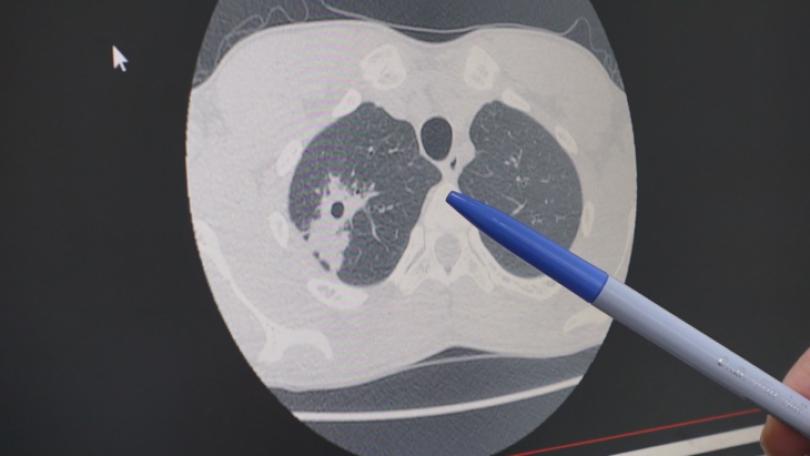

台大肺結核傳染匡列9百學生 疾管署:單一個案非校園群聚

|生活台大日前有多名學生接獲「肺結核接觸者檢查」通知信,明確指出,接觸者需依法完成衛教、胸部X光與抽血等檢查。台大校方回應,配合主管機關規定,進行肺結核防疫措施,因涉及個資不便說明細節。衛福部長石崇良證實,此案為單一確診個案,並非校園群聚,強調台大校園有一位外籍生被診斷肺結核,因此匡列接觸者,並回溯至可能感染期間,初步匡列約900人。

健保雲端系統升至2.0 導AI輔助癌症精準治療

|生活癌症已連續43年位居國人10大死因第1位。為了延長癌症存活率,健保署結合數位科技助功抗癌,今(2025)年健保雲端系統進化到2.0,強化數據互通並導入AI輔助技術,縮短癌友用藥等待時間。另外11月起更新增檢驗檢查結果圖形化查詢,例如民眾跨院所就醫不需再拷貝影像學光碟片,可避免重複檢查,也減少健保支出。